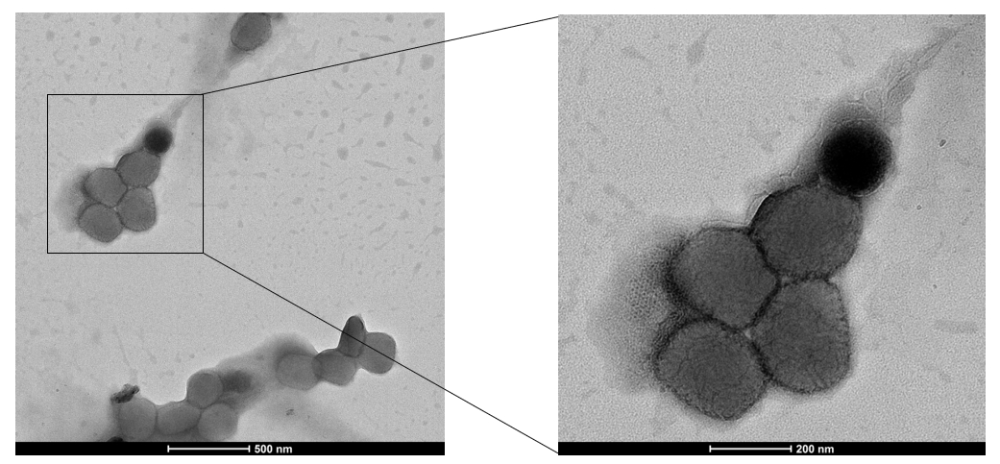

猴痘是由猴痘病毒感染所致的一种病毒性人兽共患病,临床表现主要为发热、皮疹、淋巴结肿大,其既往主要发生在中非和西非。但截至2022年10月19日,全球共累计报告了75141例感染病例,100多个国家发现猴痘病例。

登录/注册后可看大图

猴痘病毒电镜图

猴痘是由猴痘病毒感染所致的一种病毒性人兽共患病,临床表现主要为发热、皮疹、淋巴结肿大,其既往主要发生在中非和西非。猴痘已成为当前公共卫生领域最重要的正痘病毒。截至2022年10月19日,全球共累计报告了75141例感染病例,100多个国家发现猴痘病例。

目前,武汉生物制品研究所从所获临床样本中成功分理出猴痘病毒,并开始疫苗药物相关工作研究。